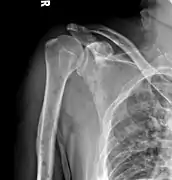

The diagnostic examination of a person with suspected multiple myeloma typically includes a skeletal survey. This is a series of X-rays of the skull, axial skeleton, and proximal long bones. Myeloma activity sometimes appears as "lytic lesions" (with local disappearance of normal bone due to resorption) or as "punched-out lesions" on the skull X-ray ("raindrop skull"). Lesions may also be sclerotic, which is seen as radiodense.[70] Overall, the radiodensity of myeloma is between −30 and 120 Hounsfield units (HU).[71] Magnetic resonance imaging is more sensitive than simple X-rays in the detection of lytic lesions, and may supersede a skeletal survey, especially when vertebral disease is suspected. Occasionally, a CT scan is performed to measure the size of soft-tissue plasmacytomas. Nuclear Medicine Bone scans are typically not of any additional value in the workup of people with myeloma (no new bone formation; lytic lesions not well visualized on nuclear bone scan).

Multiple myeloma in the upper arm